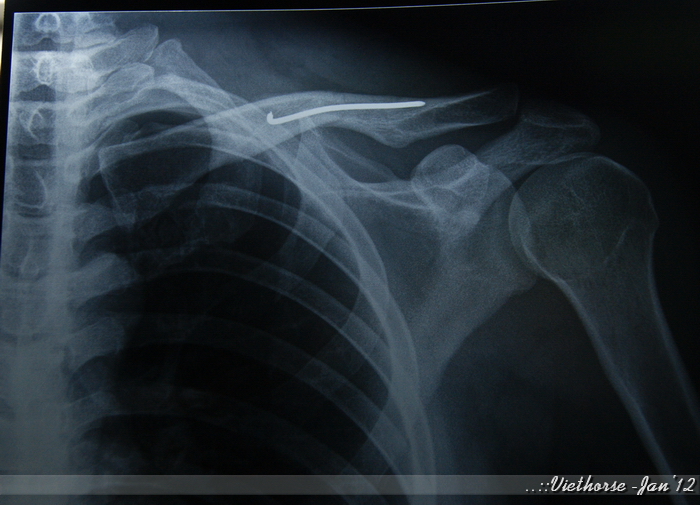

A shoulder fracture is a broken bone in the shoulder. First, your doctor will carefully check the injury to see where and how. It typically hurts more with breathing or movement of the arm. If it's broken, quick treatment can speed your recovery. Most broken shoulders can be treated without surgery. Shoulder fractures most often involve the clavicle (collarbone), proximal humerus (top of the upper arm bone), or the scapula (shoulder blade). These fractures typically occur after a fall or high impact collision. It takes three to four months for the bone to heal. Scapula fractures can be very painful in the shoulder, chest, or back. During this time, you will do exercises to get better movement and strength.